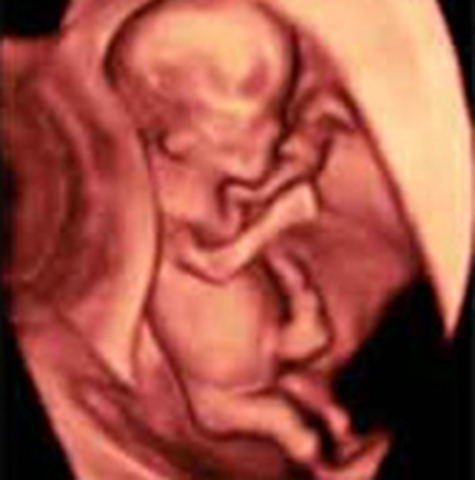

• Semana 10

Semana 10

El embrión se denomina feto en lo sucesivo, la movilidad es mucho mayor e incluye movimientos corporales y de los 4 miembros; se mueve por todo el saco gestacional lleno de líquido amniótico. Las neuronas siguen multiplicándose de manera muy rápida. Los órganos esenciales del bebé ya se han formado y el feto se hace más resistente a las lesiones externas